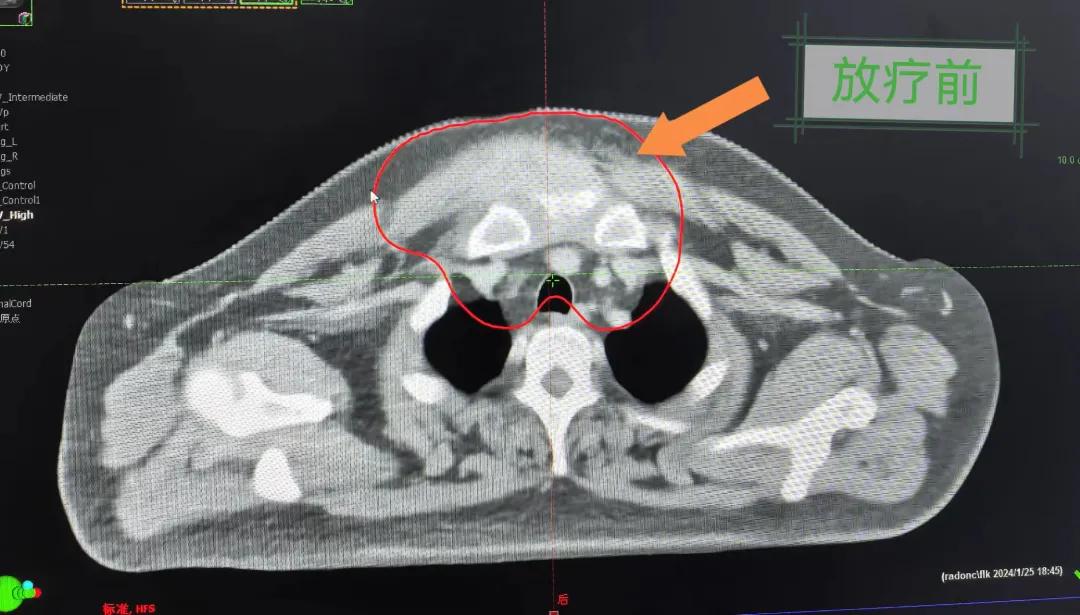

患者經(jīng)多方咨詢與打聽,在家屬的陪同下來到市二院放療科找到趙亮主任尋求幫助。入院后迅速完善了相關(guān)檢查,診斷為罕見的“胸壁腫瘤”。因腫瘤體積大,侵犯周圍組織,手術(shù)治療難度較大,經(jīng)院內(nèi)多學(xué)科會診后,決定采用無創(chuàng)的局部放射治療。在初步告知患者及家屬治療方案時,病人及家屬都擔(dān)心預(yù)后及放療可能引起的不適,趙亮主任詳細(xì)且耐心的向家屬和病人講述放療過程中可能出現(xiàn)的不良反應(yīng),確保讓他們安心治療。

隨后,趙亮主任帶領(lǐng)放療團隊以最快的速度完成了患者的放射治療計劃,在保證放療精準(zhǔn)打擊腫瘤的同時,利用先進的三維立體精確放療技術(shù),最大限度的避免心臟、肺部的損傷發(fā)生,整體治療精準(zhǔn)度達到1mm以內(nèi)。經(jīng)過10次的放射治療后,患者疼痛已明顯減輕,胸部腫物肉眼可見的縮小,患者及家屬臉上終于露出久違的笑臉。

治療期間,患者沒有出現(xiàn)明顯不適,治療結(jié)束后,患者胸壁腫物由最初8cm縮小至約1cm,后患者至外科行手術(shù)治療。